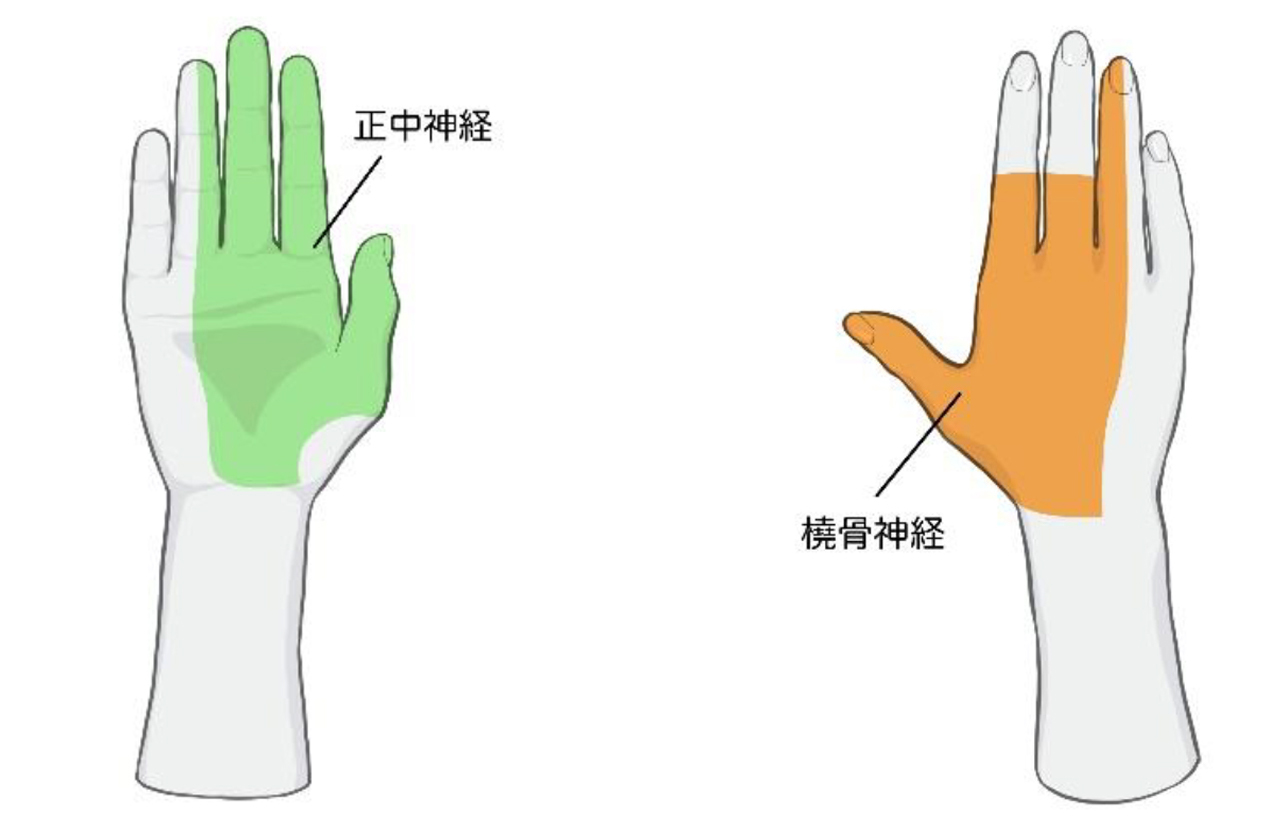

■胸郭出口症候群

手や腕を動かす神経や血管が走っている首と胸の間にある通路を胸郭出口といい、その隙間にある神経や血管が締め付けられたり圧迫されると、肩や肩甲骨周りの痛み、コリ、腕にかけてのシビレ、感覚障害が発生する疾患です。

- 腕の痛み、シビレ

- 指先の感覚障害